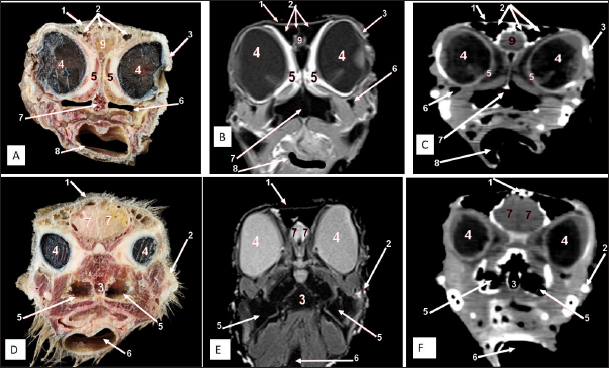

Fig. 6. Rostral-caudal cross sections of the adult ostrich head—level 1. Rostral views of A) photograph of an anatomical cross section, B) MRI and C) computed tomography images (rostral view) showing: a- Rostral nasal concha, b- Dorsal nasal recess, c- Ventral nasal recess, d- Nasal septum. Caudal views of D) an anatomical section photograph, E) MRI and F) computed tomography images showing: 1- Os nasale, 2- Os maxillare, 3- Vomer, 4- Nasal septum, 5- Infra orbital sinus, 6- Frontal sinus, 7- Mandible, 8- Tongue, a- Middle nasal concha (bulla), b- Middle nasal concha, c- Middle nasal meatus, d- Ventral nasal meatus, and e- Rostral nasal concha mucosal fold.

Fig. 7. Rostral-caudal cross sections of the adult ostrich head—level 2. Rostral views of A) photograph of an anatomical cross section, B) MRI and C) computed tomography images showing: 1- Processus.frontalis, 2- Os maxillare, 3- Vomer 4- beginning of the orbit, 5- Infra orbital sinus, a- Middle nasal concha, b- Dorsal nasal meatus, c- Ventral nasal meatus, d- Nasal septum. Caudal views of D) anatomical cross section, E) MRI, and F) computed tomography images showing: 1- Processus. frontalis, 2- Frontal sinus (separated by the median septum), 3- Lateral nasal process, 4- Processus.jugalis, 5- Nasal septum (two ridges separated by an empty groove), 6- Caudal nasal concha, 7- Ventral nasal meatus, 8- Infra orbital sinus, 9- Palate, 10- Oropharynx, 11- Laryngeal cavity, and 12- Eye ball.

Fig. 8. Rostral-caudal cross sections of the adult ostrich head—level 3. Rostral views of A) photograph of an anatomical cross section, B) MRI and computed tomography images showing: 1- Os nasalis, 2- Frontal sinus (divided by septea), 3- Lateral nasal process, 4-Os jugalis, 5- Vomer (pneumatic), 6- Nasal septum (two ridges separated by an empty groove), 7- Laryngeal cartilage, 8- Laryngeal cavity, 9- Eye ball, 10- Infra orbital sinus, 11- Choanae. Caudal view of D) an anatomical section, E) MRI and F) computed tomography images showing: 1- Os nasalis, 2- Frontal sinus, 3- Lateral nasal process, 4- Eye ball, 5- Os jugalis, 6- Pars verticalis ethmoidale, 7- Vomer, 8- Infra orbital sinus, 9-Latyngeal cartilage, 10- Tracheal lumen surrounded by tracheal cartilaginous rings.

Oropharyngeal cavity

The characteristic ostrich beak was made up of the top jaw (premaxilla) and lower jaw (mandibular symphysis and dentary bones), as well as their keratinized covers (maxillary and mandibular rhamphotheca) (Fig. 1). The beak had a triangular form with a thin rostral apex. The maxillary rhamphotheca had a median culmen and lateral tomium, whereas the mandibular rhamphotheca had a median gonys and lateral tomium (Fig. 1B and C). The oropharyngeal cavity appeared compressed dorsoventrally, similar to the shape of a bell, and supported dorsally by the palate and ventrally by the mandible. The ostrich’s tongue was tiny and located on the floor of the oropharynx (Figs. 24 and 6D). Oropharyngeal CT and MRI studies confirmed the anatomical findings. MRI provided a greater appreciation and visualization of the various soft tissue structures than CT scanning (Figs. 24 and 6E and F).

Two featherless oval nostrils were found on either side of the premaxilla and covered by a characteristic operculum at the entrance. The upper beak’s dorsal ridge (culmen) was located between both nostrils (Fig. 1A and B). The nasal cavity was cone-shaped, extending to reach the choanae. Dorsolateral bony boundaries of the nasal cavity are the frontal process of the premaxilla, nasal, and dorsal horizontal plate of ethmoidal and nasal bone’s lateral process, while the ventral boundary created by the maxillary and palatine processes of the premaxilla, maxilla, and rostral part of the pterygoid and vomer bones. The vomer bone was pneumatic. The nasal septum divides the nasal cavity into two halves and consists of caudal bony and rostral cartilaginous parts (Fig. 2).

There are three types of nasal conchae: rostral, middle, and caudal (Figs. 35). The rostral nasal concha extended to reach the middle third of the nasal cavity (Fig. 3), and it was partially visible through the nostrils (Fig. 1B). The cross-section showed a T-shaped projection linked to the nasal cavity’s lateral wall, forming dorsal and ventral recesses. The rostral concha extends caudally beneath the rostral section of the middle nasal concha, forming the middle nasal meatus. At the floor of the nasal cavity, there is a feature mucous membrane fold connecting the rostral concha to the nasal septum (Fig. 6).

The middle nasal concha was more prominent than the rostral concha. It was situated on the caudo-dorsally to rostral one and resembled a coiled or bulla-shaped structure. The middle nasal concha was located in the middle of the nasal cavity, between the dorsal and middle nasal meatus (Figs. 3,4,5,6D, and 7A).

The caudal nasal concha is the smallest triangular one. In cross-section, it appeared scroll-like, attached rostrally to the middle one, making it difficult to differentiate between them. While caudally, the ventral nasal meatus was connected to the infraorbital sinus and the oropharyngeal cavity by two slits (or holes) in the palate called choanae.

Two paranasal sinuses were detected, triangular-shaped infraorbital and two identical frontal sinuses as the infraorbital paranasal sinus was identified as a triangular chamber rostroventral to the orbit (Figs. 3 and 8A), while the frontal paranasal sinuses were positioned dorsally, separating the cranial and nasal cavities. There were two frontal sinuses, one on the right and one on the left, separated by a bone septum in the center. The frontal sinuses were found between the frontal and nasal bones, dorsally and laterally, between the lacrimal and vertical plates of the ethmoidal bone (Figs. 2, 3, 4, 7D, 8, and 9A). All last structures were compared and verified by CT and MRI, to guarantee precise identification and labeling; the anatomical section structures for each cross-section level were matched to their corresponding MRI and CT images. In CT images, the bones appeared white (high CT density), the gaseous parts were black (the lowest attenuation), and the soft tissue was grey (low-to-intermediate CT density). In MR images, bones appeared white (high signal intensity), the gaseous parts were black (no signal intensity), and the soft tissue was grey (low-to-intermediate signal intensity).

The nasal conchae exhibited in the MRI images as bright (high or hyperintense signal intensity) to gray (low or hypointense signal intensity) structures that could be divided into three parts: rostral, middle, and caudal conchae, which correlated to the morphological examinations. In contrast, the nasal conchae could not be recognized clearly on CT images compared to those obtained after MRI (Figs. 25 B and C). The paranasal sinuses with other structures could be identified using both CT and MRI. The nasal septum and paranasal sinuses revealed a white bone border (high signal intensity), soft tissue was grey (low-to-intermediate signal intensity), and they contained black gas, so both the CT and MRI scans showed little signal intensity (Figs. 15B and C and 79B, C, E, F).